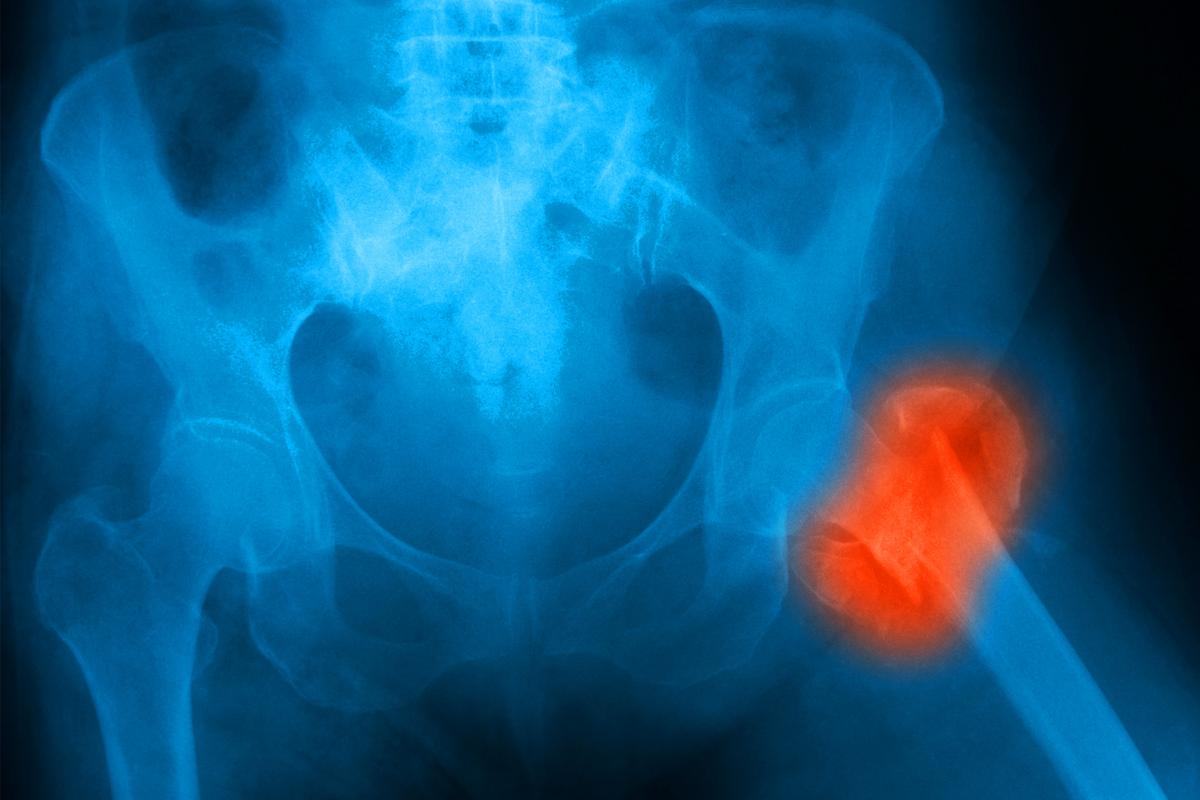

New osteoporosis screening guidelines maintain recommendations for women 65 and older to get bone density tests but raise fresh concerns about overdiagnosis and the reliability of risk assessments for younger postmenopausal women, according to an updated evidence review from the U.S. Preventive Services Task Force (USPSTF).

According to 2018 guidelines from the USPSTF, women aged 65 and older should be screened for osteoporosis using bone density testing, and postmenopausal women younger than 65 with an increased risk of fractures should also be screened using a clinical risk assessment tool.